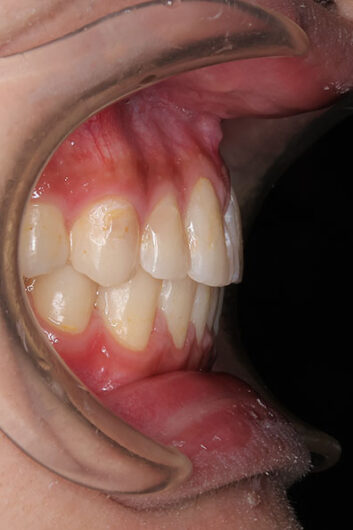

受け口を気にされ、他院からの紹介で来院された患者さんです。

小学2年生、生え変わりの時期から小児矯正を開始しました。

小児矯正で前歯の咬み合わせを改善し、

永久歯列完成後の中学生から非抜歯治療にて本格矯正を開始。

配列し仕上げました。